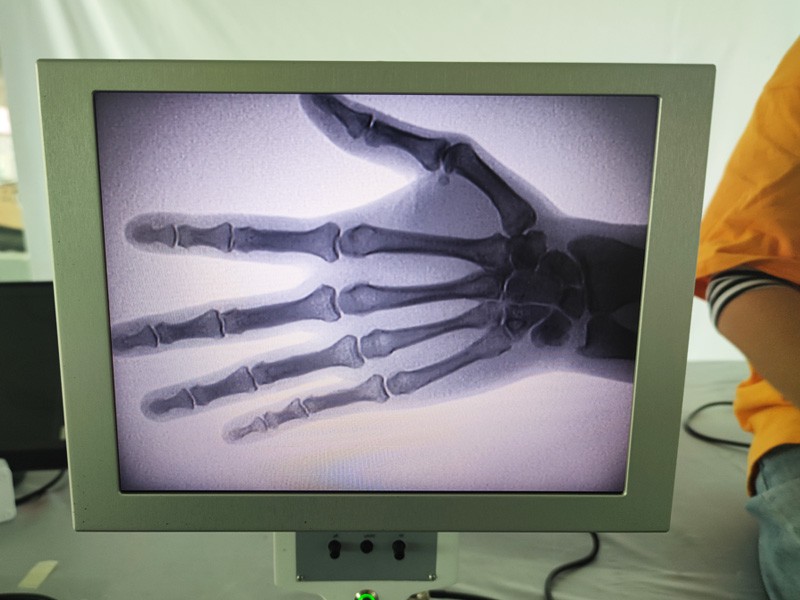

Das tragbare Röntgengerät As-c200 ist ein tragbares Instrument mit geringer Strahlendosis und sehr sicher. Es eignet sich besonders für Einheiten und Einzelpersonen mit unzureichendem Budget und geringen Anforderungen an Bilder. Die neue Generation ist mit einem 10-Zoll-HD-Großbildschirm ausgestattet, der einen größeren Perspektivbereich bietet und die gesamte Handfläche vollständig perspektivisch betrachten kann. Es ist vor allem aus medizinisch-orthopädischer Sicht geeignet. Es kann an einen Foliendrucker angeschlossen werden, um orthopädische Folien zu bedrucken, und kann auch in der industriellen Produktion und Prüfung eingesetzt werden. Keine Dunkelkammer, direkte Perspektive, sofortige Beobachtung, hohe Auflösung und klare Bildgebung.

Bei unserem orthopädischen Röntgengerät handelt es sich um ein hochwertiges Produkt, das speziell für die orthopädische Bildgebung entwickelt wurde. Es kann zur Diagnose und Behandlungsplanung verschiedener orthopädischer Erkrankungen verwendet werden, darunter Frakturen, Luxationen, Arthritis und Knochentumoren. Es ist mit fortschrittlicher Röntgentechnologie ausgestattet, die qualitativ hochwertige Bilder bei reduzierter Strahlenbelastung ermöglicht. Das Gerät verfügt über ein hochauflösendes Bildgebungssystem und kann Bilder jeder Knochenstruktur mit großer Klarheit aufnehmen.

3. Große Bildanzeige: Das Gerät verfügt über eine große Bildanzeige, die einen effizienten Arbeitsablauf und eine einfache Identifizierung kritischer Befunde ermöglicht.

Unser orthopädisches Röntgengerät kann in verschiedenen medizinischen Fachgebieten eingesetzt werden, darunter Orthopädie, Neurologie und Notfallmedizin. Es wird häufig zur fluoroskopischen Beobachtung menschlicher Gliedmaßenknochen, in Veterinär- und Tierkliniken sowie zur Behandlung von Verwundeten an Sportstätten, in Gebäuden, auf Hochseeschiffen, in abgelegenen Gebieten und auf Militärgeländen eingesetzt. Zu den klinischen Anwendungen gehören: